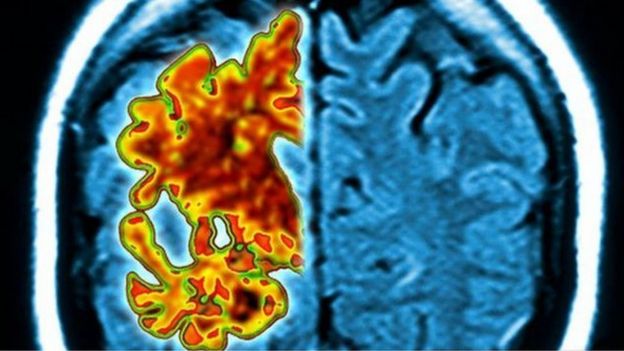

目前对该病的诊断往往是在患者已经出现症状时,医生通过记忆力测试和脑部扫描相结合的方法进行确诊。

阿尔茨海默氏病破坏大脑神经细胞之间的连接,由于蛋白质在大脑中积累并导致神经细胞死亡,因此会破坏记忆力和认知能力。